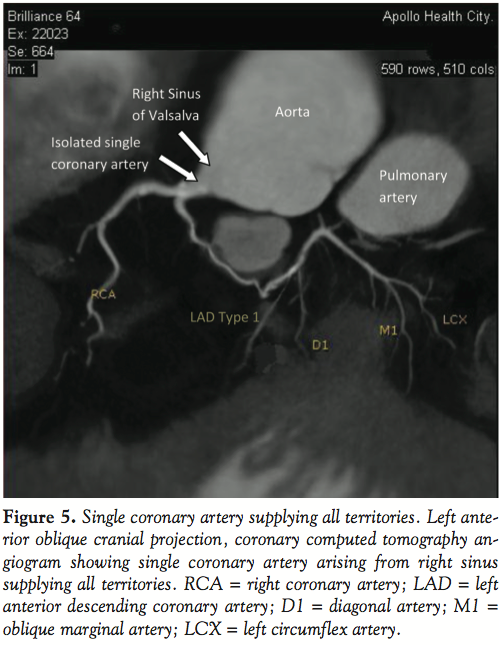

A 59-year-old man with a history of hypertension, family history of premature coronary artery disease and atypical chest heaviness was referred to exercise stress test. After achieving 89% target heart rate at a workload of 9 metabolic equivalents using Bruce protocol, 1–1.5 mm horizontal ST depressions were seen in the lateral leads. Coronary angiogram revealed a single coronary artery originating from the right sinus of Valsalva; this artery bifurcated into a right coronary artery and an anomalous left main coronary artery. Multi-detector row computed tomography confirmed the same findings. The anomalous left coronary artery followed a pre-pulmonary course anterior to the pulmonary trunk to supply the anterior descending, diagonals and circumflex artery. There was no evidence of an inter-arterial course, which is considered malignant. The coronary arteries were free of atherosclerotic disease. Stress myocardial perfusion imaging showed no inducible ischemia. Echocardiogram showed normal left ventricular function.

The overall incidence of single coronary artery disease in a series of consecutive angiograms is between 0.024%1 and 0.044%.2 An aberrant left main artery arising from a single coronary artery from the right sinus of Valsalva (R-II-A as per modified Lipton classification) was seen in 4 cases out of a series of 50,000 angiograms.3